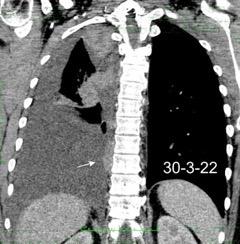

Marzo 2014: Perforación longitudinal distal secundaria a episodio de vómito (síndrome de Boerhaave). Derrame pleural izdo. que evoluciona a empiema.

Wang C-T et al. Tension hydropneumothorax in a Boerhaave syndrome patient: A case report . World J Emerg Med, 2021. Katabathina V et al. Nonvascular, nontraumatic mediastinal emergencies in adults:a comprehensive review of imaging findings. Radiographics. 2011.